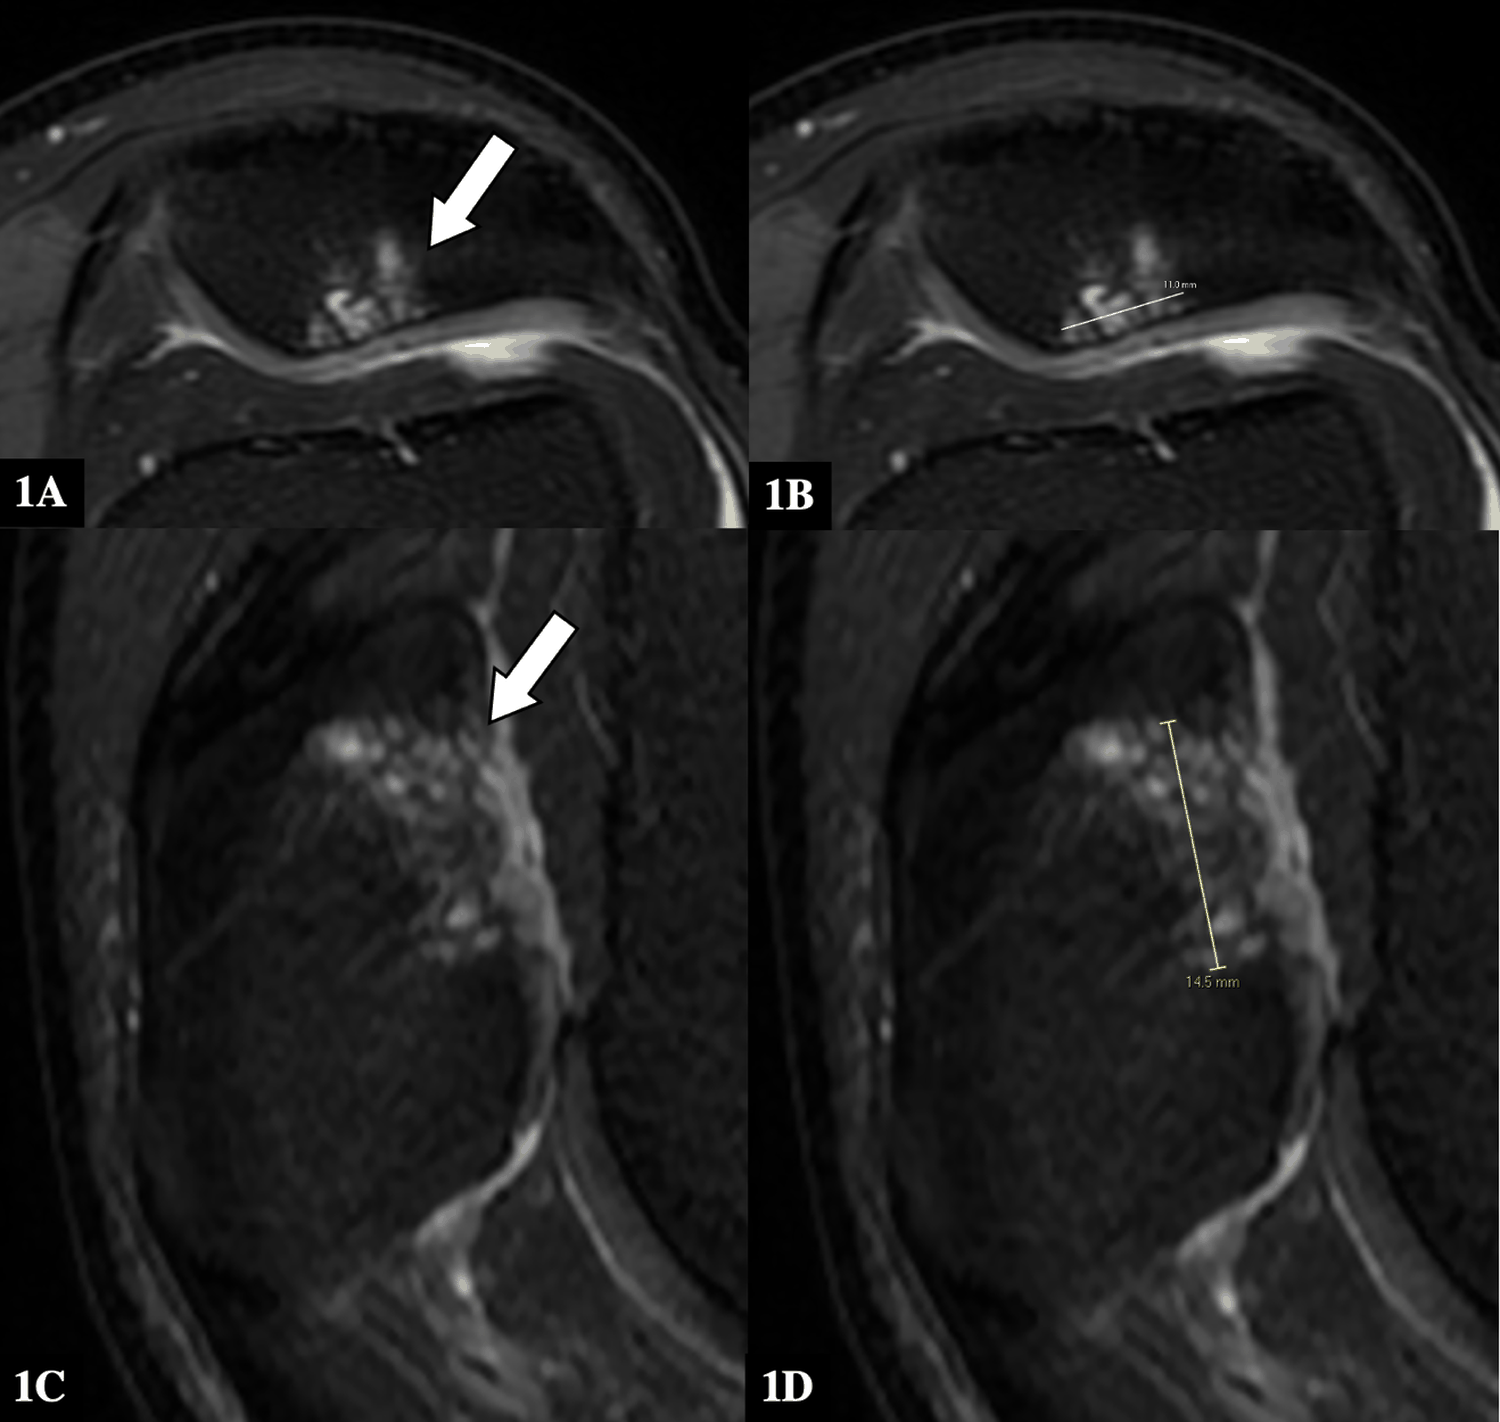

Utilizing Clinical Examination in Conjunction with Magnetic Resonance Cartilage Studies for Post-Operative Evaluation of Cartilage Repair: A Case Report

Stefanie Hui Ting Lee, Cynthia Assimta Peter, Steven Bak Siew Wong, Adriel Guang Wei Goh

1-10